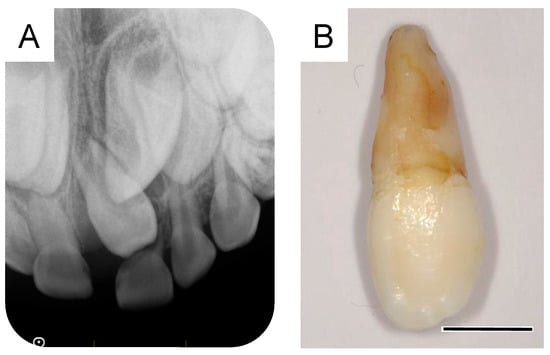

Orthodontic treatment was considered after the extraction of the third supernumerary tooth; however, the patient was uncooperative because of his intellectual disability. At 8 years and 9 months of age, a periapical radiograph revealed no change in the location of the permanent maxillary left central incisor (Figure 5A,B). Thus, under physical restraint and local anesthesia, the gingiva was surgically removed using an electrocautery device to expose the surface of the crown (Figure 5C).

Following surgical exposure, the incisor gradually erupted in the oral cavity (Figure 6). At 9 years and 7 months of age, as confirmed by radiographic examination, no new supernumerary tooth had reoccurred. Intraoral examination revealed mesial inclination of the permanent maxillary left central incisor and a space shortage for the maxillary incisors (Figure 7). The patient is gradually showing an improvement in readiness for dental treatment. Therefore, long-term follow-up will be performed, and orthodontic treatment will be considered according to the wishes of the patient and parents.

Figure 5. Fenestration of the maxillary left central incisor. (A) Intraoral photograph and (B) periapical radiograph after the extraction of the third supernumerary tooth at the age of 8 years and 9 months. (C) Intraoral image just after fenestration of the maxillary left central incisor at the age of 8 years and 9 months.

Figure 6. Intraoral photographs of the postoperative period. (A) One month after surgical exposure creation (8 years and 10 months of age). (B) Two months after surgical exposure creation (9 years and 0 months). (C) Four months after surgical exposure creation (9 years and 2 months).